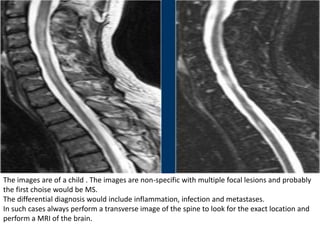

The images are of a child . The images are non-specific with multiple focal lesions and probably

the first choise would be MS.

The differential diagnosis would include inflammation, infection and metastases.

In such cases always perform a transverse image of the spine to look for the exact location and

perform a MRI of the brain.

The lesions are located dorsally and one of the lesions is enhancing.

Now if this was infection or metastases it would be strange that not all lesions enhance.

MS is still on our list.